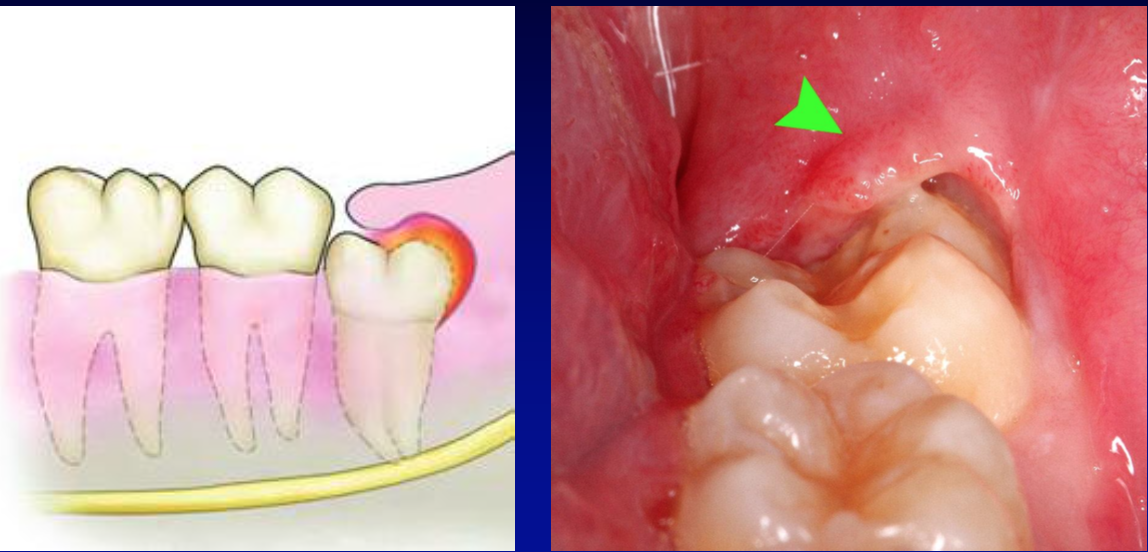

pericoronitis

special type of acute periodontal abscess that occurs when gingival tissue (operculum) overlies an erupting tooth (usually a third molar)

recurring acute symptoms are usually initiated by trauma from the opposing tooth or by impaction of food or debris under the flap of tissue that partially covers the erupting tooth

pericoronitis procedure

relieving the pain is surgical removal of the operculum. Inject local anesthetic directly into the overlying tissue and then cut it away using the outline of the tooth as a guide for the incision. Sutures are not required

irrigate w/ a weak (3%) hydrogen peroxide solution

purulent material can be released by placing the catheter tip of the irrigating syringe under the tissue flap overlying the impacted molar

prescrive oral analgesics for comfort as well as penicillin over the next 10 days

instruct the patient on the importance of cleansing away any food particles that collect beneath the gingival flap

follow-up should be provided to observe the resolution of the acute infection and to evaluate the need for removal of the gingival flap or molar

DO NOT undertake any major blunt dissection while draining pus. This could spread a superficial infection into the deep spaces f the head and neck or follow a deep abscess posteriorly into the carotid sheath